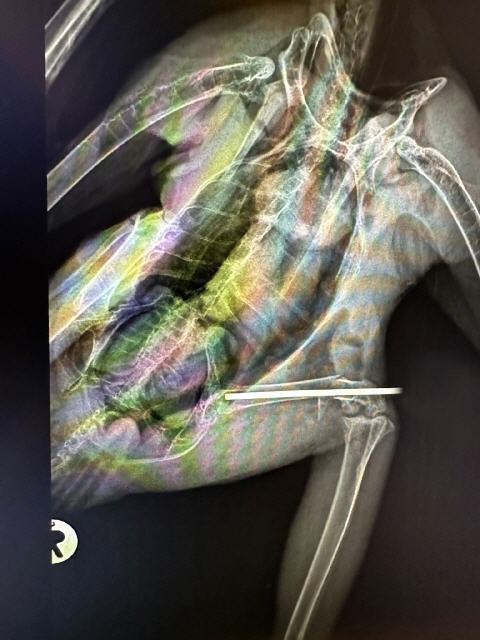

Geglückte OP bei Stockente

Die Stockente wurde nach einem Zusammenstoß mit einem Auto aufgesammelt und zu einer Vogelfreundin gebracht. Diese ist eine langjährige Kundin von mir und weiß, dass ich ebenfalls ein großer Vogelliebhaber bin. Die Vogelfreundin unterstützt die Praxis seit vielen Jahren bei der Pflege und Auswilderung von Wildvögeln, für sie kam eine Euthanasie nicht infrage. Ich sollte versuchen, den Ruderfuß der Ente zu retten, was glücklicher Weise auch gelang. Wir hoffen nun, dass sich die Stockente rasch erholt.